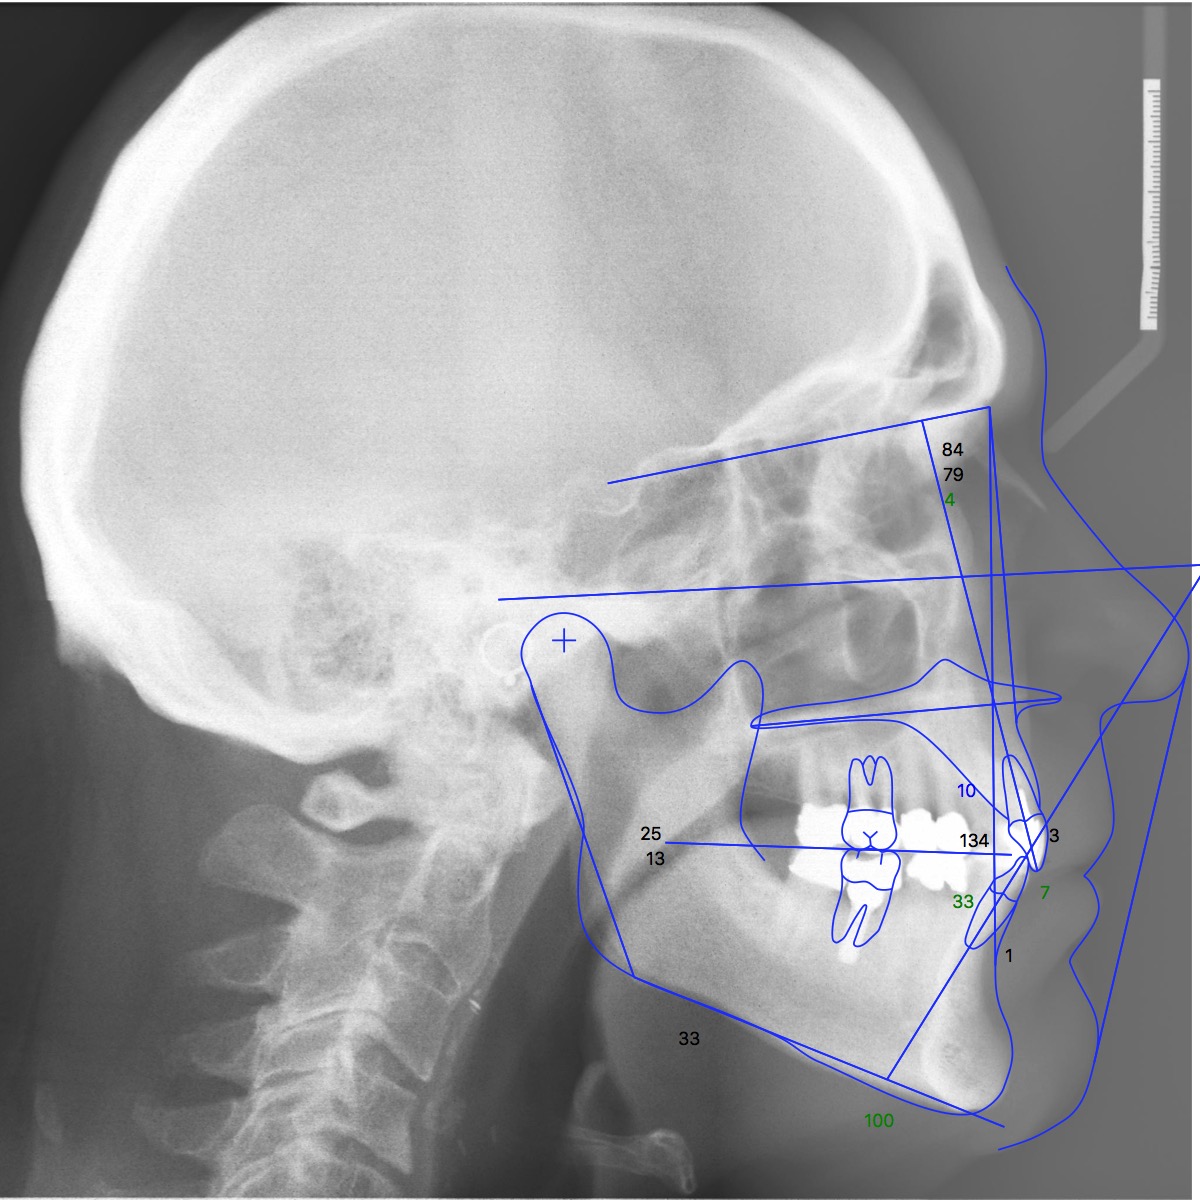

• Smile optimization. When optimizing the smile position of the upper anterior teeth, using cephalometric analysis can provide a more consistent evaluation than a subjective impression of underlying jaw and tooth relationships. Due to the excessive interincisal angle present in this case, the removable aligners were programmed with lingual root torque for the upper anterior teeth (Figure 5 and Figure 6).

(5.) Postorthodontic cephalometric analysis.

Figure 5